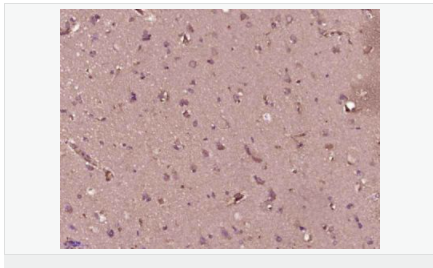

| 產品應用 | WB=1:500-2000 ELISA=1:5000-10000 IHC-P=1:100-500 IHC-F=1:100-500 IF=1:100-500 (石蠟切片需做抗原修復) not yet tested in other applications. optimal dilutions/concentrations should be determined by the end user. |

| 產品介紹 | The encoded protein is a homolog of yeast securing proteins, which prevent separins from promoting sister chromatid separation. It is an anaphase-promoting complex (APC) substrate that associates with a separin until activation of the APC. The gene product has transforming activity in vitro and tumorigenic activity in vivo, and the gene is highly expressed in various tumors. The gene product contains 2 PXXP motifs, which are required for its transforming and tumorigenic activities, as well as for its stimulation of basic fibroblast growth factor expression. It also contains a destruction box (D box) that is required for its degradation by the APC. The acidic C-terminal region of the encoded protein can act as a transactivation domain. The gene product is mainly a cytosolic protein, although it partially localizes in the nucleus. Three transcript variants encoding the same protein have been found for this gene. [provided by RefSeq, Sep 2013]. Function: Expressed at low level in most tissues, except in adult testis, where it is highly expressed. Overexpressed in many patients suffering from pituitary adenomas, primary epithelial neoplasias, and esophageal cancer. Subcellular Location: Cytoplasm. Nucleus. Post-translational modifications: Phosphorylated at Ser-165 by CDK1 during mitosis. Phosphorylated in vitro by ds-DNA kinase. Ubiquitinated through 'Lys-11' linkage of ubiquitin moieties by the anaphase promoting complex (APC) at the onset of anaphase, conducting to its degradation. 'Lys-11'-linked ubiquitination is mediated by the E2 ligase UBE2C/UBCH10. Similarity: Belongs to the securin family. SWISS: O95997 Gene ID: 9232 Database links: Entrez Gene: 9232 Human Entrez Gene: 30939 Mouse Omim: 604147 Human SwissProt: O95997 Human SwissProt: Q6IAL9 Human SwissProt: Q3Y5K4 Mouse SwissProt: Q5SRU0 Mouse SwissProt: Q9CQJ7 Mouse Unigene: 350966 Human Unigene: 6856 Mouse Unigene: 137183 Rat Unigene: 271 Rat Important Note: This product as supplied is intended for research use only, not for use in human, therapeutic or diagnostic applications. 垂體腫瘤轉化基因PTTG可在多種腫瘤組織及部分正常組織細胞內表達較高,對促進細胞增殖、轉化及腫瘤發(fā)生有重要作用。 |